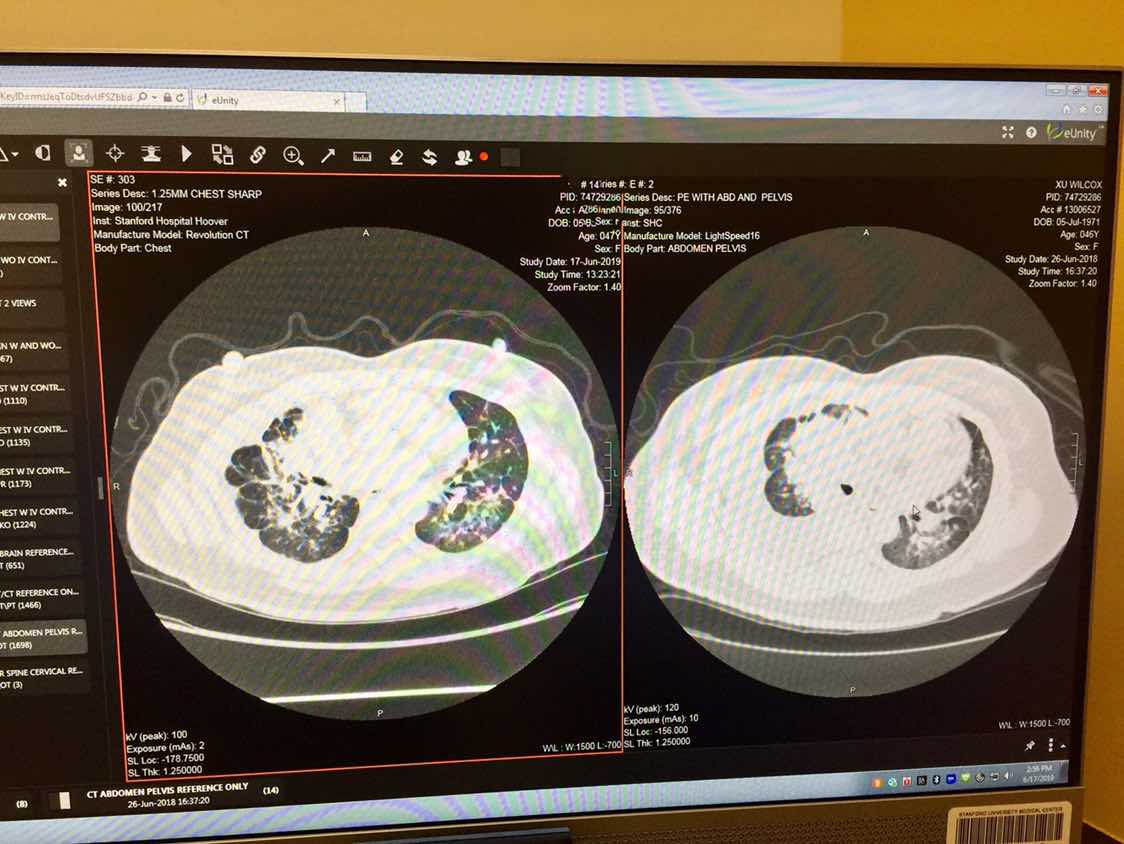

这个看起来好棒是好了很多啊,但是不在一个层面上

不是一个层面的,无法对比。还是拿片子直接找专科医生来看靠谱。

这应该是部分缓解了